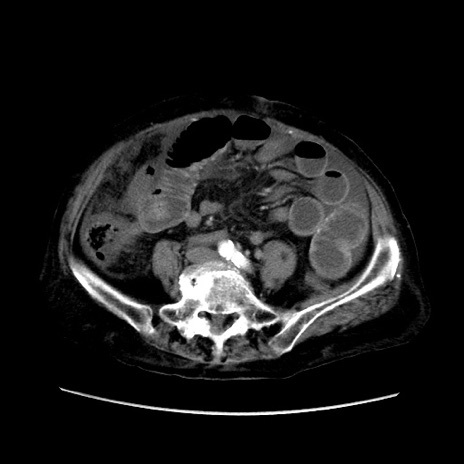

症例31(横断像)

【症例】80歳代 女性

【主訴】腹部膨満感

【現病歴】他院にて肝硬変にてフォロー中。1週間前から便秘、腹部膨満感、臍部腫瘤あり受診となる。

【既往歴】肝硬変

【身体所見】腹部膨隆あり、皮膚変化なし、疼痛なし。

【データ】WBC 4600、CRP 0.25